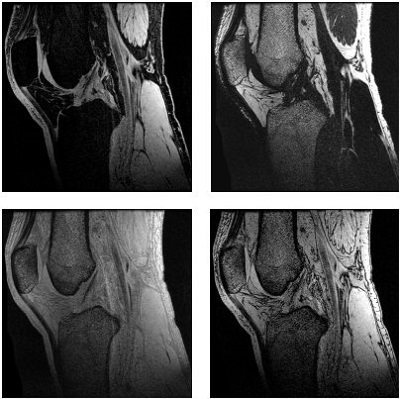

A proton’s exact resonance frequency depends on its chemical environment. Hydrogen attached to oxygen, as in water, experiences a magnetic field that is slightly different from that of hydrogen bonded to carbon in fat. This causes a well-known displacement artifact occurring at boundaries of water and fat-containing tissues.

Displacement artifacts are caused by spins in water and fat containing tissues having slightly different resonance frequency. The effect is an artifact void on one side where the two structures meet and an artifact signal enhancement where the signal intensities from the two structures add.

| Number | Description |

|---|---|

| 1 | Fat |

| 2 | Water |

| 3 | Void |

| 4 | Enhancement |

| 5 | Phase |

| 6 | Frequency |

Fat and water images are slightly displaced relative to one another, causing an artificial increase and decrease, respectively, at the locations of misalignment. The displacement artifact, which occurs in the frequency encoding direction, varies based on the field strength and receive bandwidth and frequency matrix scan parameters.

Acquiring images with a fat or water suppression technique reduces chemical shift artifacts because these artifacts are caused by relative shifts of fat from water. When one component is suppressed, there is nothing for the other component to shift away from.